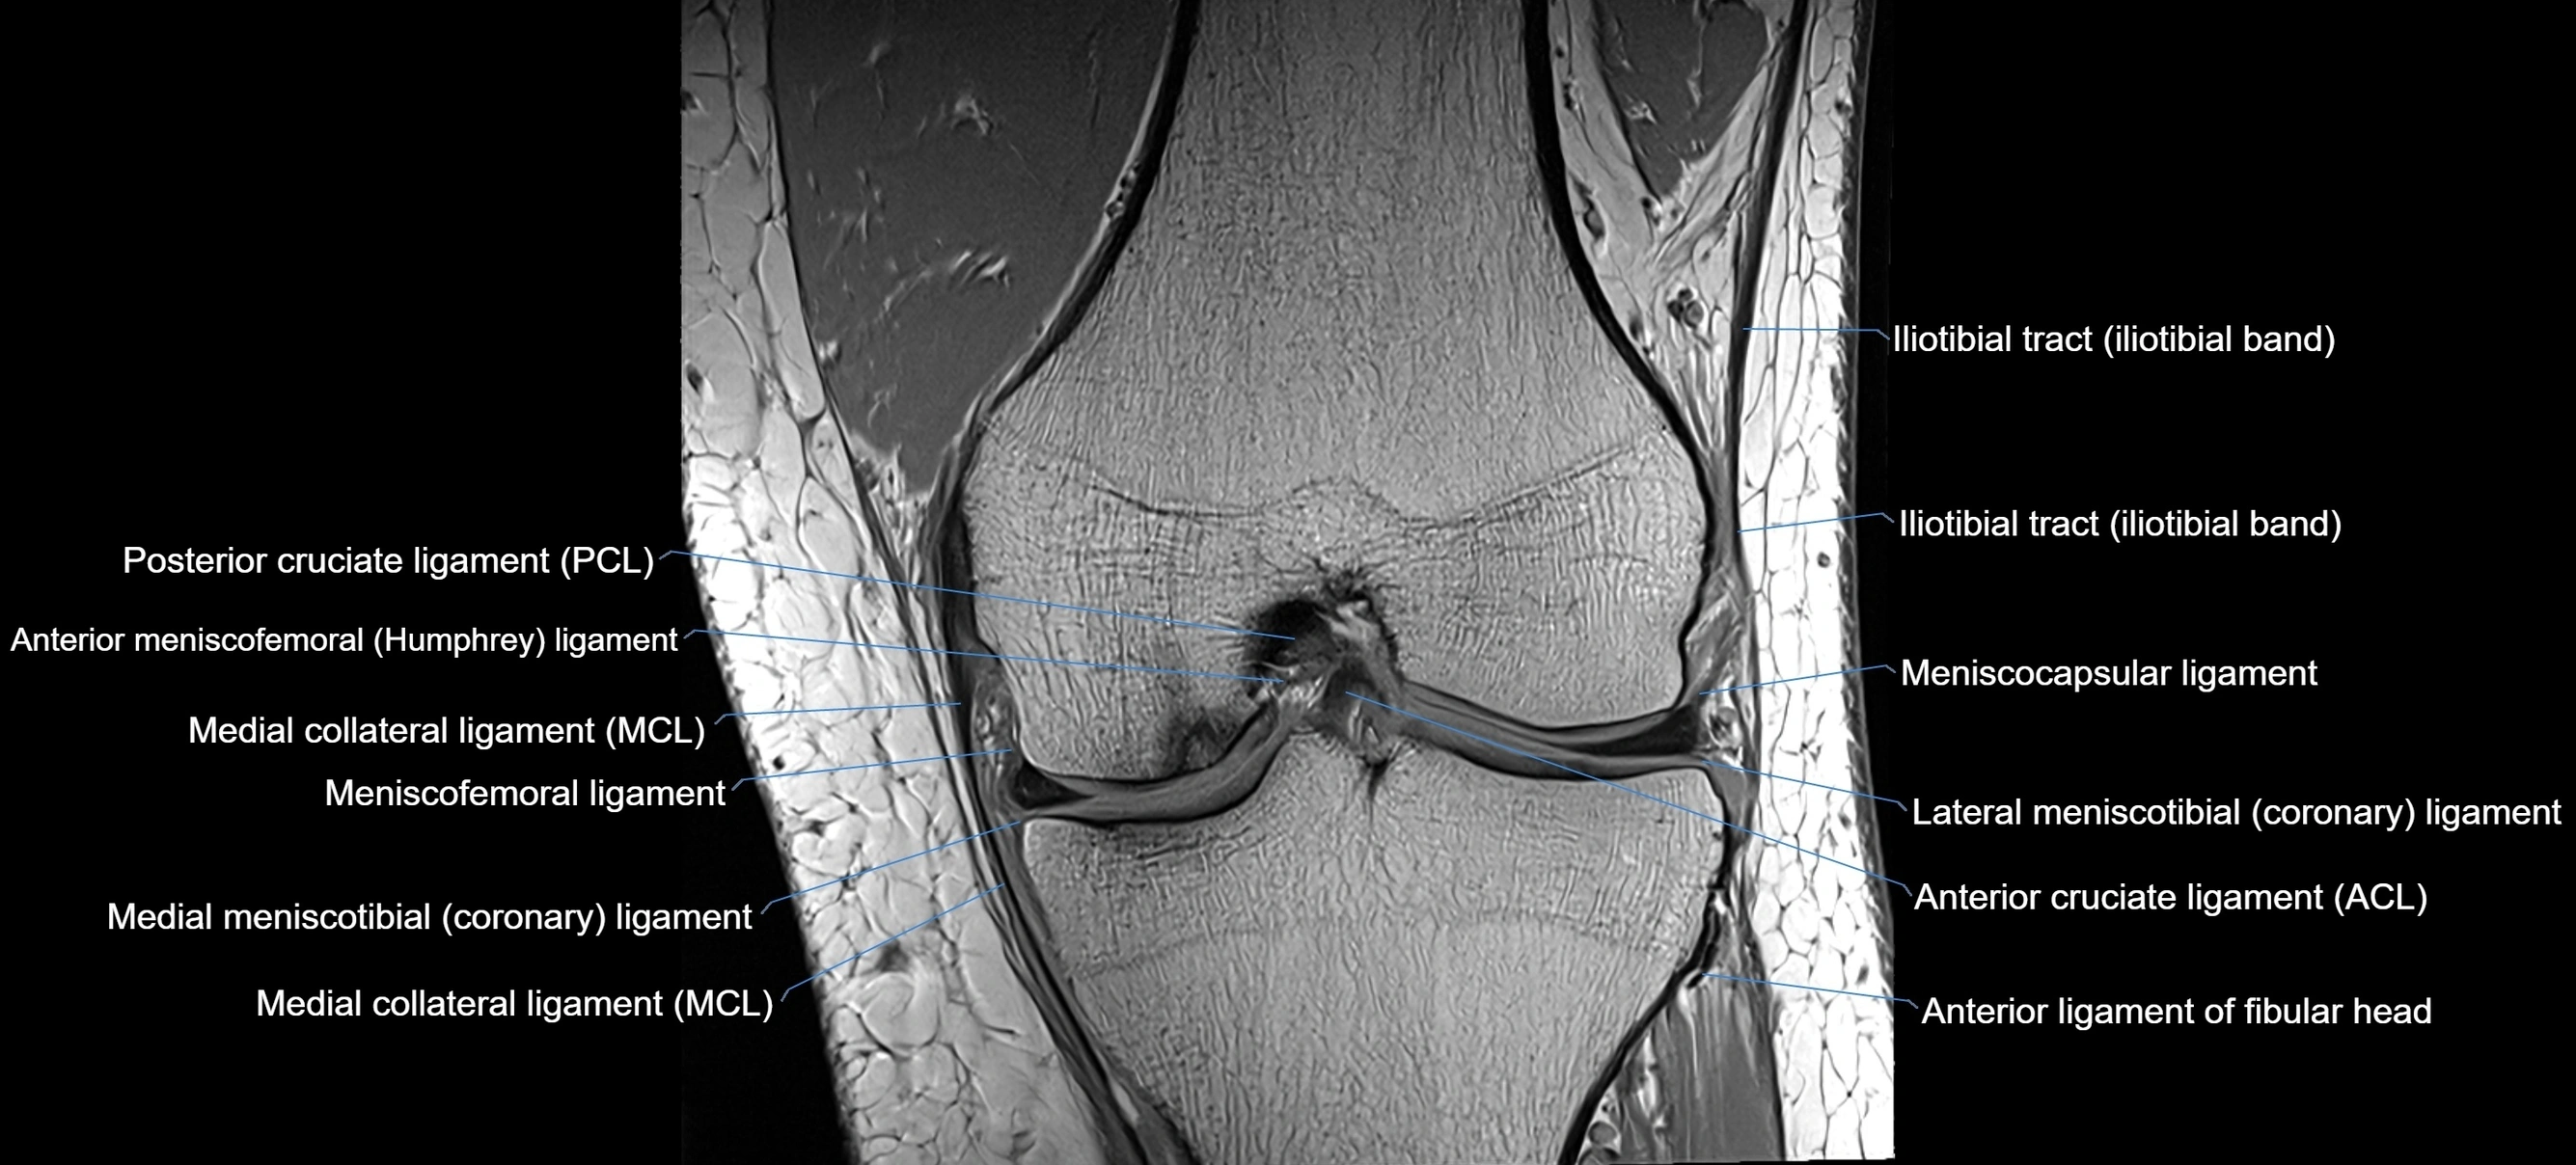

MRI images

image

MRI Appearance

T1-weighted images:

• Normal ACL appears as a low-signal band-like structure crossing the intercondylar notch

• Surrounded by intermediate signal synovial fluid and fat planes

T2-weighted images:

• Normal ACL remains low signal

• Partial or complete tears appear as discontinuity, increased signal, or fiber laxity